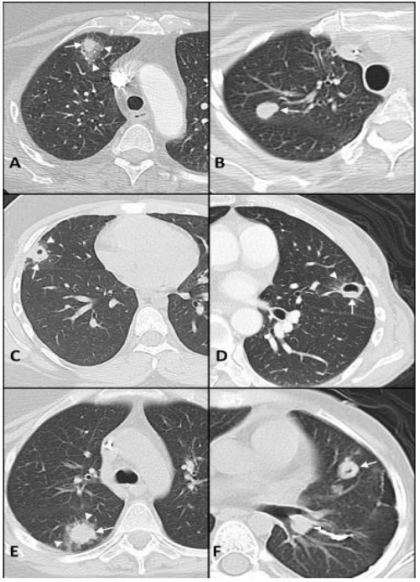

军团菌肺炎影像学特点: ①军团菌肺炎影像学表现不具有特异性, 实变是其常见的影像学发现; ②相对特异性的表现为磨玻璃影中混杂边缘相对清晰的实变影, 各肺叶均可受累; ③1/3的病例可合并胸腔积液。

3所示为文献报道的较为典型的军团菌影像学表现:A为70岁女性,右肺上叶实性结节伴磨玻璃影;B为41岁女性,右上肺叶有实心结节;C为17岁男性,右中叶结节伴中央空洞,伴磨玻璃影;D为51岁女性,舌叶结节,中心空洞,周围磨玻璃影;E为35岁女性,右下肺叶结节和周围磨玻璃影;F为7岁女性,舌叶结节,中央有空洞。

图片

3  文献报道中军团菌影像学表现